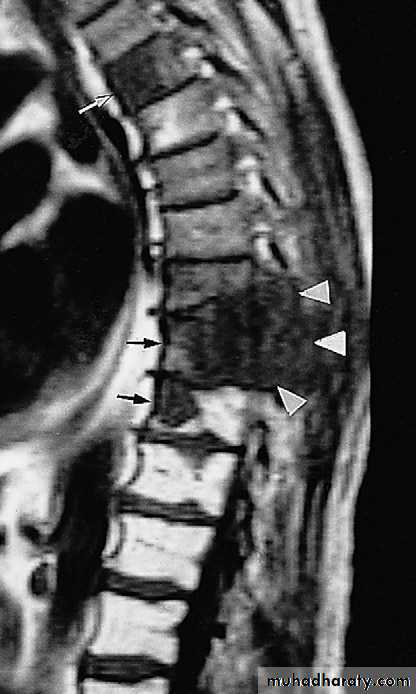

MRI is better than radionuclide scanning for the detection of metastases, but it is more difficult to survey the whole skeleton .Multiple myeloma :

frequently seen in bones with active haemopoiesislesions .may resemble lytic metastases in every way but are often better defined- diffuse marrow involvement may give rise to generalized loss of bone density

MRI has good role in detecting multiple myloma lesions .